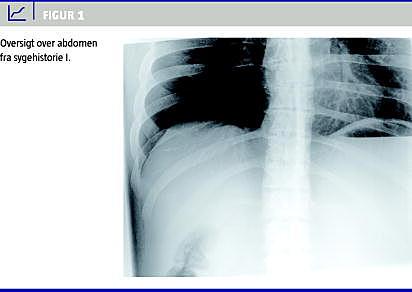

I. En 28-årig mand, som et år tidligere har fået foretaget laparoskopisk gastrisk bypass, blev indlagt akut. Han har i fire dage haft kvalme, opkastningsfornemmelser og intermitterende abdominale smerter. Ved indlæggelsen var der konstante smerter, som var lokaliseret til øvre abdomen. I hele perioden var der normal tarmfunktion. Abdomen var spændt og øm, men uden peritoneal reaktion. Oversigt over abdomen tolkedes primært som normalt (Figur 1 ). Kontrastindgift viste fri og hurtig passage af kontrasten. Patientens tilstand forværredes den følgende time med tiltagende smerter, takykardi og påskyndet respiration. Der var normalt blodtryk, og temperaturen måltes til 35,1 °C (aksiltemperatur). Der foretoges derefter akut operation med fund af svært dilateret ventrikel, flere liter blakket væske intraperitonealt, som kom fra den udshuntede del af ventriklen, hvor der er opstået lækage ved stapler- rækken på grund af en stenose i det ileopankreatiske ben ved jejunojejunostomien. Der anlagdes en gastrostomi, og et stenotisk jejunumstykke på fem cm recesseredes, og afslutningsvis anlagdes der en ny jejunojejunostomi. Der blev givet firestof-antibiotika for sepsistilstanden, og de første dage var patienten på intensiv afdeling. Patienten rettede sig hurtigt, og det postoperative forløb herefter var ukompliceret. Gastrostomisonden seponeredes efter fire uger.

Ved gastrisk bypass deles ventriklen i to. Den øverste del af ventriklen anastomoseres til jejunum, idet jejunum deles ca. 75 cm fra Treitz' ligament, og den anale del af jejunum føres op til pouchen antekolisk og antegastrisk. Dette alimentære ben forenes med det bileopankreatiske ben ca. 100 cm nede. Resten af tyndtarmen ned til terminale ileum benævnes »fællesbenet« (common limb ). Tidlige procedurespecifikke komplikationer er specielt anastomoselækage og blødning. Sene alvorlige kirurgiske komplikationer til gastrisk bypass er især ulcus svarende til gastrojejunostomien, interne hernier samt stenose svarende til gastrojejunostomien eller jejunojejunostomien. Stenose i det alimentære ben kan sædvanligvis behandles konservativt, men stenose i det bileopankreatiske ben udgør et særligt problem. Komplikationen opstår i 0,07-0,9% tilfælde [3, 4]. Tilstanden kan udvikles akut, men der vil typisk være en udvikling af symptomer over nogle dage med tiltagende ubehag, fornemmelse af kvalme og trang til opkastning, som dog på grund af den ændrede anatomi ikke kan lade sig gøre. Ved tiltagende udspiling af ventriklen på grund af det hæmmede afløb kommer der manglende gennemblødning og efterhånden iskæmi i ventrikelvæggen, ventrikelindholdet bliver purulent, der kan udvikles pankreatitis og intrahepatisk stase med kolangitis og sepsis. Ved røntgenoversigt over abdomen kan der ses en udspilet ventrikel, en diagnose som i Sygehistorie I blev overset. Bedste diagnostiske tiltag er akut computertomografi. I sygehistorie I forekom der en drastisk forværring af patientens tilstand på mindre end en time, hvilket understreger vigtigheden af akut undersøgelse og behandling. Hvis diagnosen stilles tidligt i forløbet, kan der anlægges en ultralydsvejledt gastrostomisonde. Herefter kan man i rolig fase recessere stenosen og anlægge en ny jejunojejunostomi. Hvis patienten når at få gastric blow-out , er behandlingen laparotomi eller laparoskopi med anlæggelse af gastrostomi og udførelse af en ny jejunojejunostomi. De septiske komplikationer er potentielt livstruende, og dødsfald til denne komplikation er beskrevet [4].